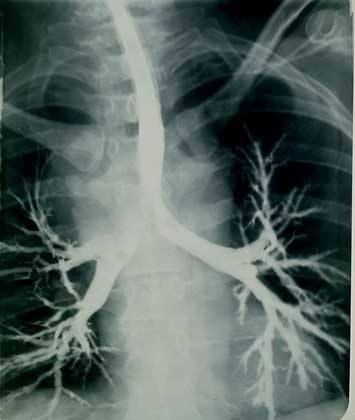

Рентгенологическими признаками асбестоза служат линейно-сетчатая деформация легочного рисунка, прикорневой фиброз, плевральные изменения (бляшки, сращения, выпот), в поздних стадиях - «сотовое легкое». При сомнительных результатах рентгенографии легких прибегаю к проведению КТ легких высокого разрешения, позволяющей достоверно рассмотреть субплевральные линейные, очаговые или неправильной формы тени.